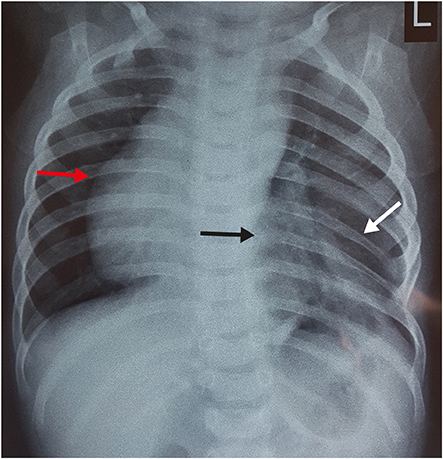

A plain radiograph chest X-ray (

Fig. 1) was suspicious of bowel loops or stomach herniating into the left hemithorax. With a working diagnosis of congenital diaphragmatic hernia (CDH)/hiatus hernia, the patient was planned for emergency surgery. The patient was explored through a left subcostal incision. There was no diaphragmatic defect. Although the left diaphragm was higher up in position, it was normal, thick and muscular and not thin and redundant, as in diaphragmatic eventration. There was no paraesophageal or sliding hernia. The spleen was found to be free from its ligamentous attachments. On palpation, of the left chest wall, the lower ribs and costal cartilages were absent along with a portion of the lower sternum. There were deficiency and absence of attachment of pectoral muscles in that region creating a 4×3 cm size muscular defect, which was repaired with non-absorbable sutures. The post-operative period was uneventful and the child was discharged 5 days later. During follow up, the child was evaluated with CT chest with 3D reconstruction (

Fig. 1 X-ray chest suggestive of bowel loops herniating into thoracic cavity (black arrow), hypoplastic 7th and 8th rib (white arrow) compare to opposite side and dextrocardia (red arrow).

In the index case, costal cartilages of lower ribs were absent with hypoplasia of 7th and 8th rib, which created a muscular defect through which lung was herniating and was causing recurrent respiratory symptoms. On the chest radiograph, the muscular defect with lung herniation was mistaken for bowel loops entering the thoracic cavity, giving the impression of diaphragmatic hernia and the dextrocardia was mistaken for the secondary mediastinal shift (

Fig. 1). Routinely, in cases of CDH, the symptomatic child requires only an X-ray chest as radiological investigation before emergency surgery. In the index case, the muscular defect was not visible with the naked eye. It may have been detected during the clinical examination at first visit if the condition had been suspected and palpation was done with prior knowledge of the condition. Although the treatment would have remained the same, i.e., closure of the muscular defect, chest wall and rib anomalies require proper pre-operative work up in the form of CT chest with 3D reconstruction.